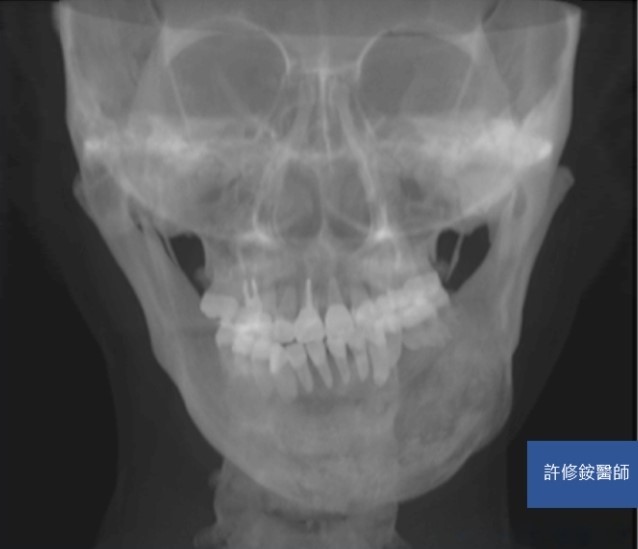

削骨手術需要精密的診斷與計算,加上顏面骨骼有特殊的圓弧與角度,精確的影像是基本要求。3D影像可協助醫師能檢視不同的切面,且影像重組後,專科醫師可自由旋轉影像由各種不同的角度檢視骨骼的變異,除了能完整地檢視病人的顏面骨並精準的訂定治療計劃;客人也能在手術前,藉由3D影像的模擬更理解醫師的解釋內容。

正顎、削骨手術需要精密的診斷與計算,加上顏面骨骼有特殊的圓弧與角度,精確的影像是基本要求。感謝科技進步,3D影像使醫師能檢視不同的切面,且影像重組後,醫師可自由旋轉影像由各種不同的角度檢視骨骼的變異。因此,醫師能完整地檢視病人的顏面骨並精準的訂定治療計劃。病人也能藉由3D影像的模擬更理解醫師的解釋內容。